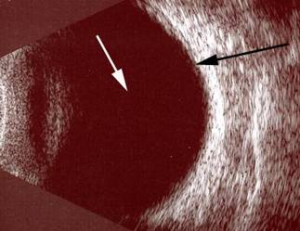

Bazı durumlarda retina, normal fundus muayenesi ile net seçilemeyebilir. Bu gibi durumlarda, göz ultrasonografisi çekilir.

Resim 8: Normal göz ultrasonografi görüntüsü. Beyaz ok göz sıvısını (vitreus), siyah ok retina tabakasını göstermektedir.